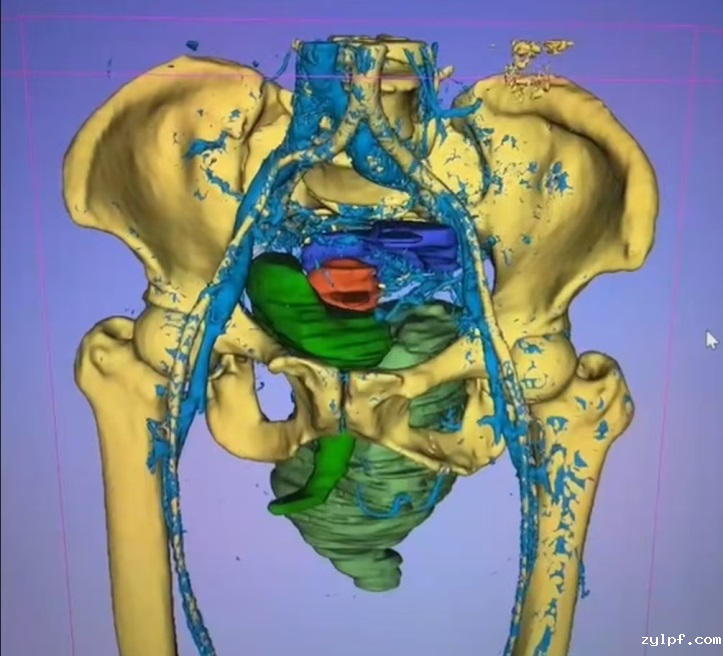

患者为54岁女性,自幼发现全身多发皮肤、皮下结节,并持续增多、变大,其中左臀部肿物尤为明显,因短时间内生长迅速、影响正常行走和排便功能来诊。患者体表可见大量散在皮肤结节、牛奶咖啡斑,MRI提示肿物信号混杂,膀胱、子宫、直肠明显受压右移,CT示该肿物跨盆腔内外,较大层面范围约13.5×8.7×13cm,密度欠均,夹杂囊变,累及左侧闭孔内肌、梨状肌、肛提肌及左侧外阴。

图片 12.png

图片 13.png图片 11.png

经过与胃肠外科、泌尿外科、妇科等多学科专家讨论,决定对该肿物进行扩大切除术。该手术难点主要在于:1.肿瘤巨大,瘤体血供丰富,且临近骶静脉丛,出血风险极高;2.肿瘤与盆腔内脏器、髂血管、坐骨神经等重要结构关系密切。因肿物与直肠下段、肛门及阴道分界不清,肛提肌受累,需切除直肠下段及肛门行永久性造瘘,首先由我院胃肠外科团队完成腹腔镜下直肠、肛门切除术+结肠造口术。经过腹腔镜探查,泌尿外科、妇科团队确认肿物未累及膀胱、子宫等其他盆腔内脏器,由骨科团队在术前3d建模辅助下完成左臀部、盆底肿物扩大切除术。